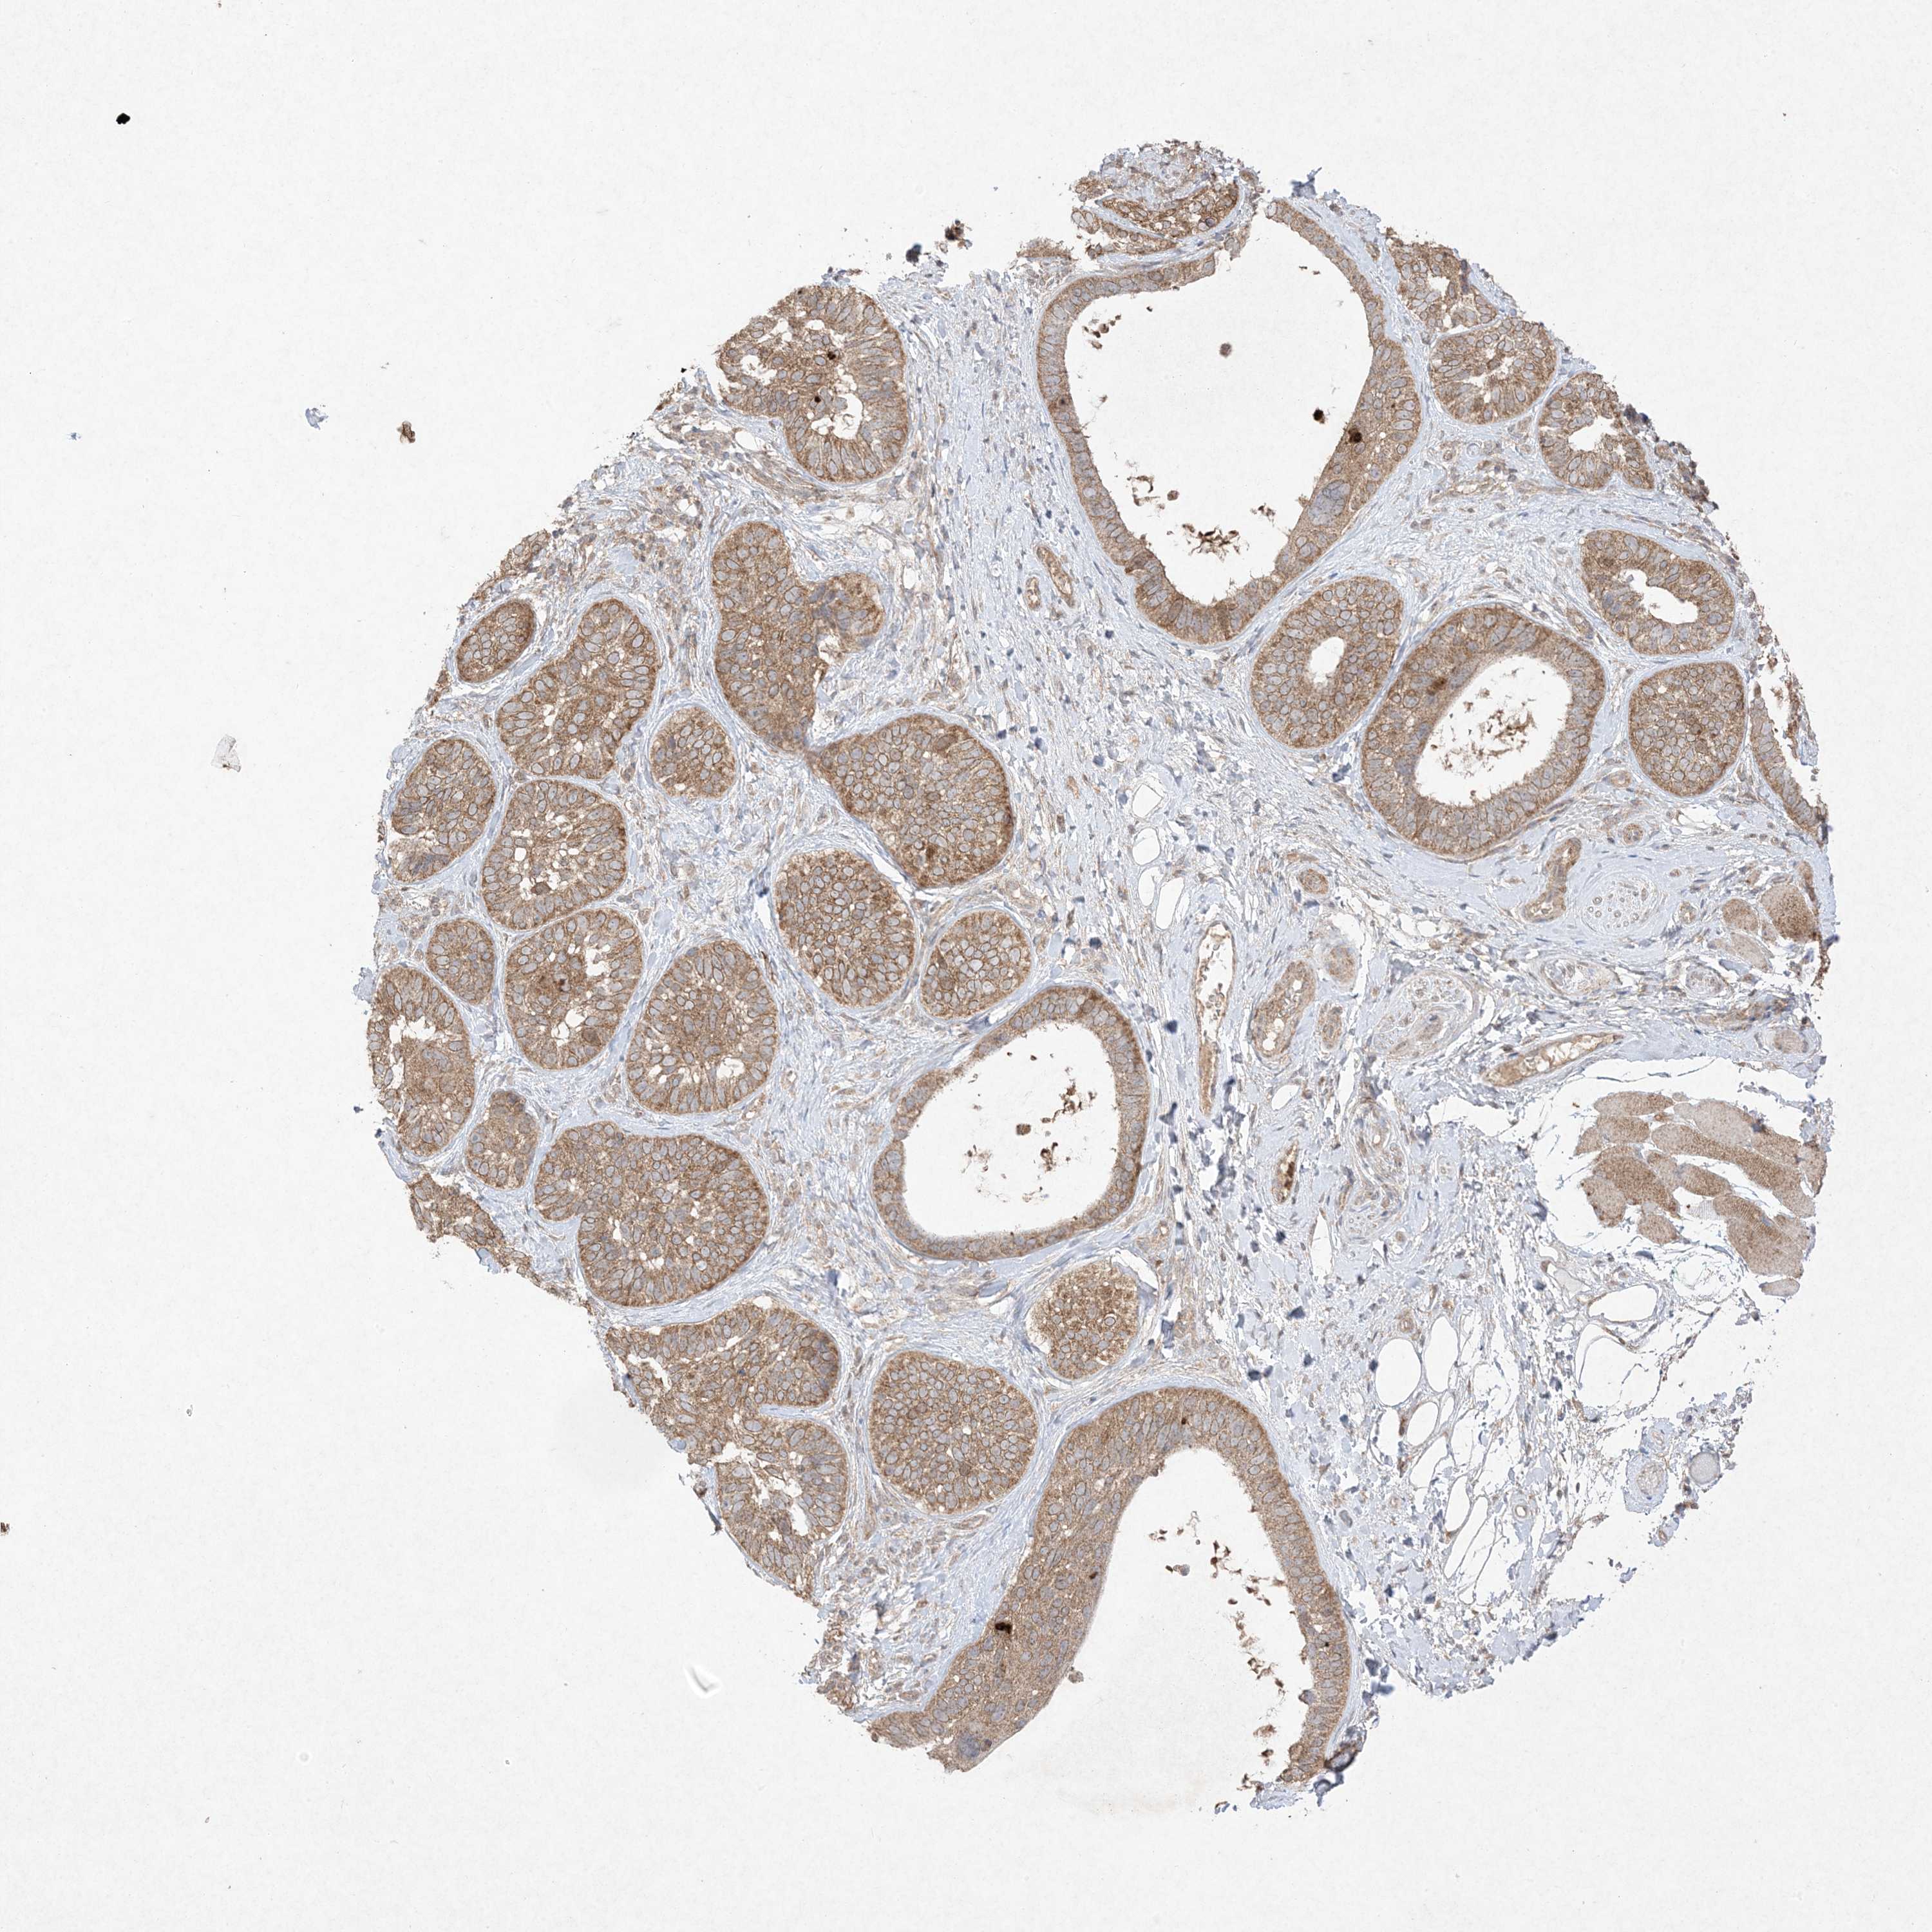

SKIN CANCER - Protein expressioni

A mouse-over function shows sample information and annotation data. Click on an image to view it in a full screen mode. Samples can be filtered based on level of antibody staining by selecting one or several of the following categories: high, medium, low and not detected. The assay and annotation is described here.

Each image is clickable and will lead to virtual microscopy that enables deeper exploration of all samples and also displays staining intensity scores, fraction scores and subcellular localization as well as patient and tissue information for each sample.

Antibody HPA054975

Antibody CAB011464

Antibody CAB035990

Antibody CAB080407

Staining

High

Medium

Low

Not detected

Squamous cell carcinoma, metastatic, NOS